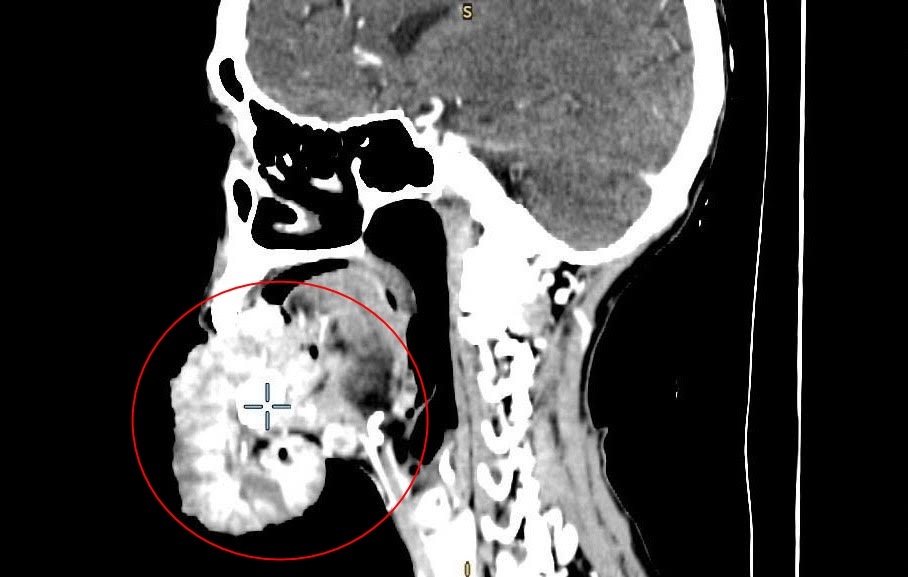

Kết quả phim chụp cắt lớp vi tính cho thấy khối u vùng môi dưới kích thước lớn 15x20 cm, xâm lấn xương hàm dưới, sàn miệng, lưỡi; di căn nhiều hạch cổ hai bên kích thước 2-3 cm. Bà Y. được chỉ định nhập viện với chẩn đoán ung thư môi dưới.

Khối u dưới cằm bệnh nhân Y. phát triển với kích thước lớn trong 3 năm bà theo đuổi chế độ thực dưỡng. Ảnh: BVCC.